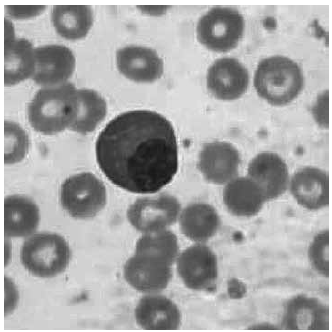

Paciente masculino, 56 anos, com fortes dores ósseas e inchaço nas pernas, realizou exames para investigação. Apresentou valores de lactato desidrogenase elevado 350,0 UI/L e, no hemograma, encontrou-se a celularidade atípica ilustrada a seguir.

Imagem: Lâmina de esfregaço sanguíneo

(Imagem gentilmente cedida pelo Laboratório de Análises Clínicas da FMABC do Centro Universitário FMABC)

Os resultados do exame de eletroforese de proteínas também estão descritos a seguir.

Diante desses achados laboratoriais, sugere-se investigação da seguinte patologia: